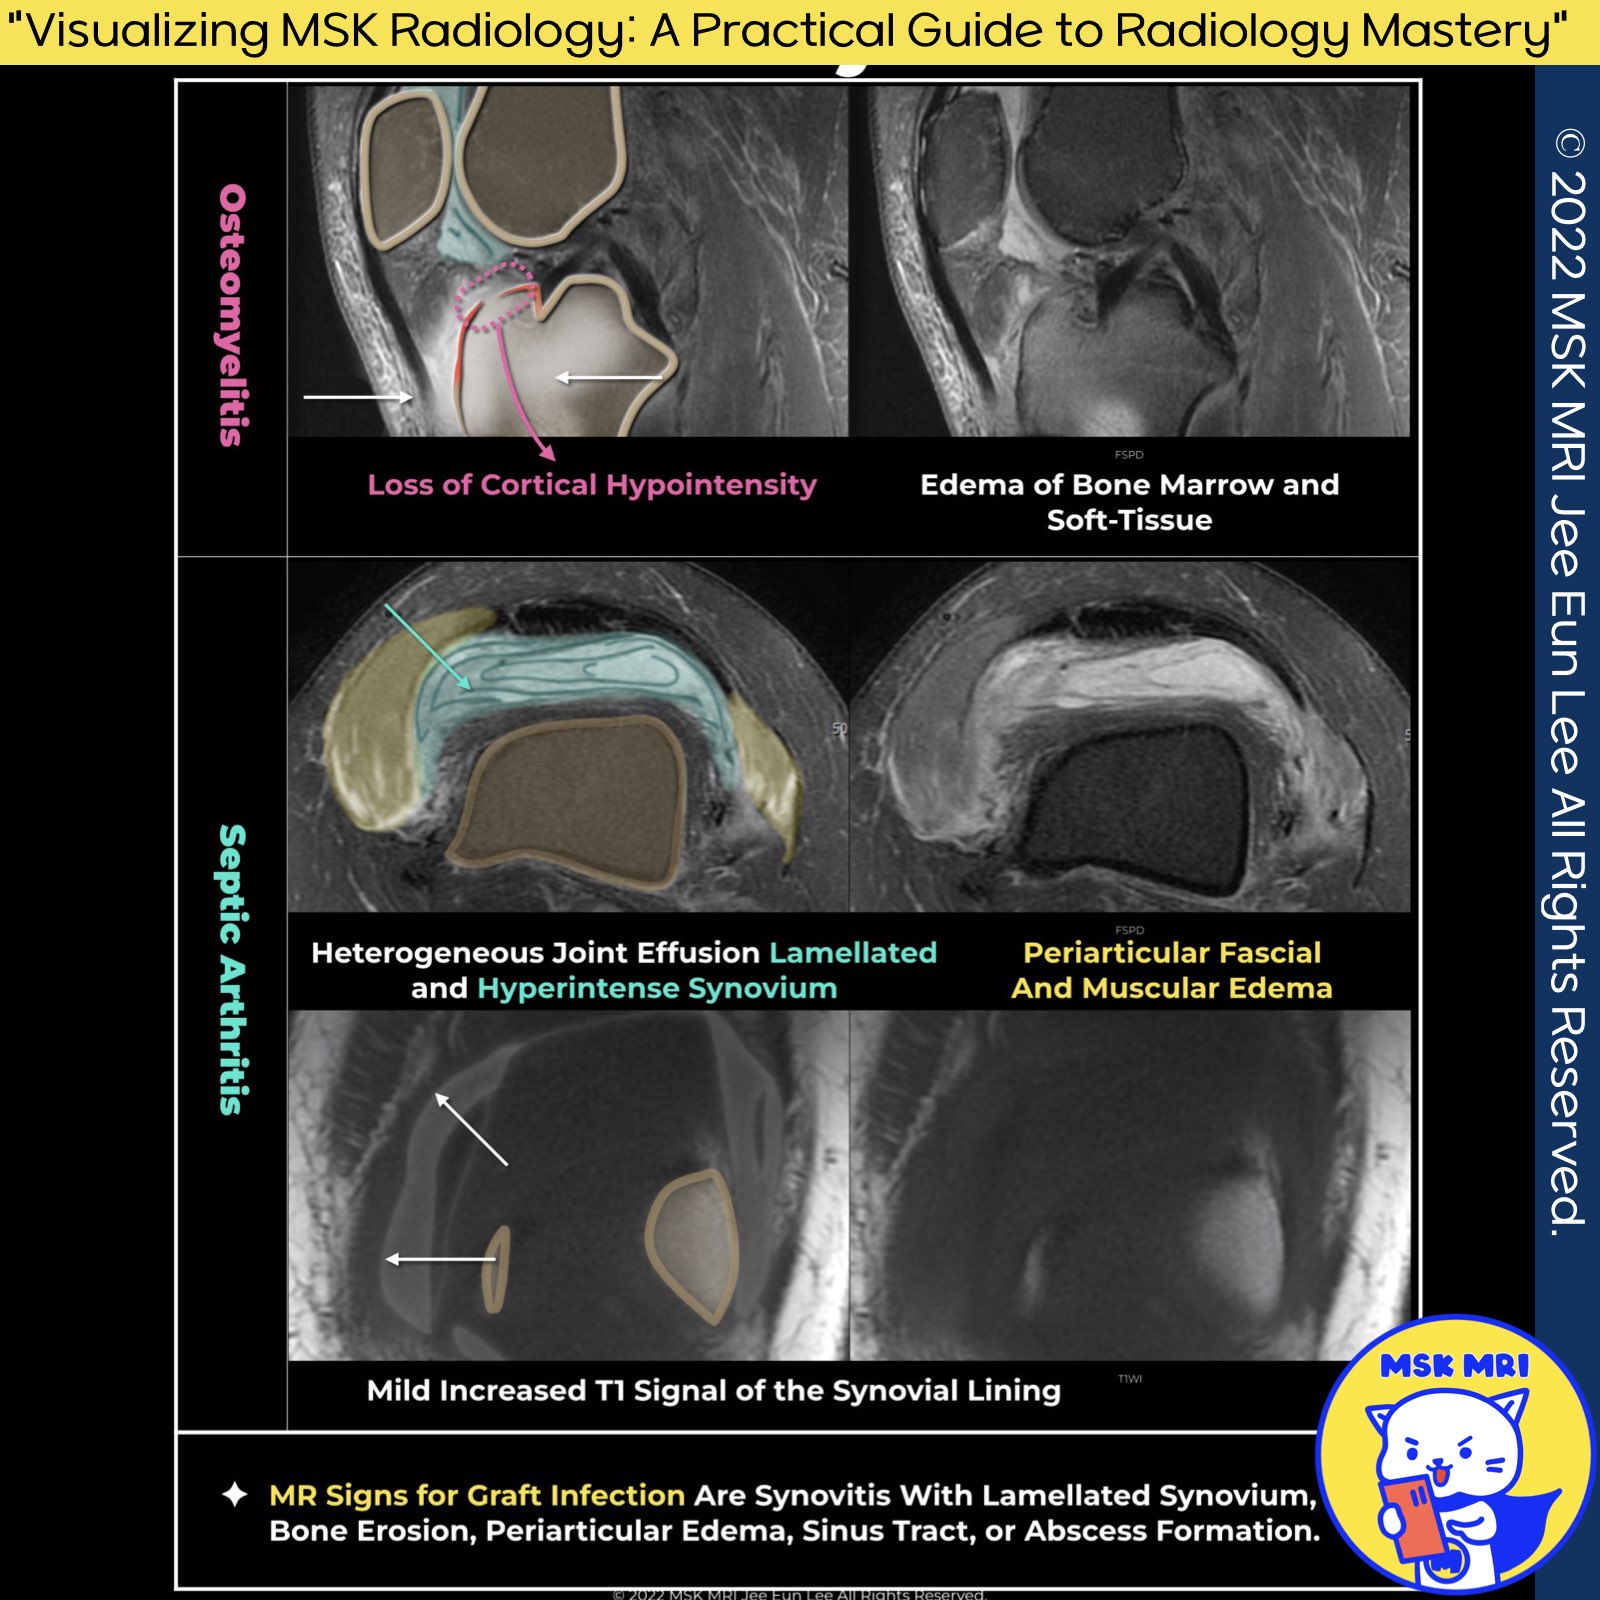

1️⃣ Graft Infection after ACL Reconstruction

- Graft infection following Anterior Cruciate Ligament Reconstruction (ACLR) is rare, with an incidence rate of 0.1–0.9%.

- These infections are most commonly identified in the early postoperative phase.

2️⃣ MRI Signs of Graft Infection

- Synovitis with Lamellated Synovium: Indicative of inflammation within the synovial membrane.

- Bone Erosion, Periarticular Edema

Bone Erosions of the Tunnels: A loss of cortical hypointensity in the tunnels can be observed, suggesting infection. - Sinus Tract Formation, Abscess Formation

- Periarticular Fascial Edema

- ACL graaft: Focal or diffuse increases in signal intensity on T2-weighted MRI images can indicate fibrinous exudates on the graft surface.